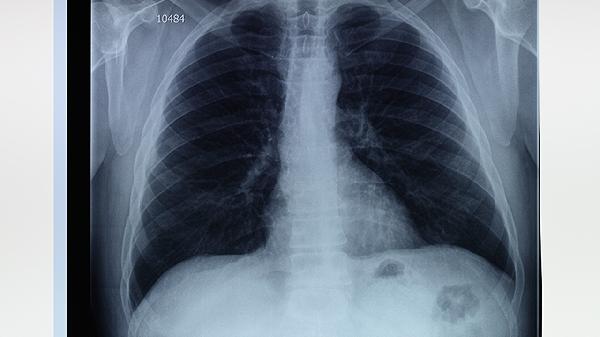

3、气胸的诊断:气胸的诊断主要依靠胸部X线检查,X线片上可见胸腔内气体影,肺部被压缩。CT检查可以更清晰地显示肺大泡的位置和大小,有助于确定治疗方案。